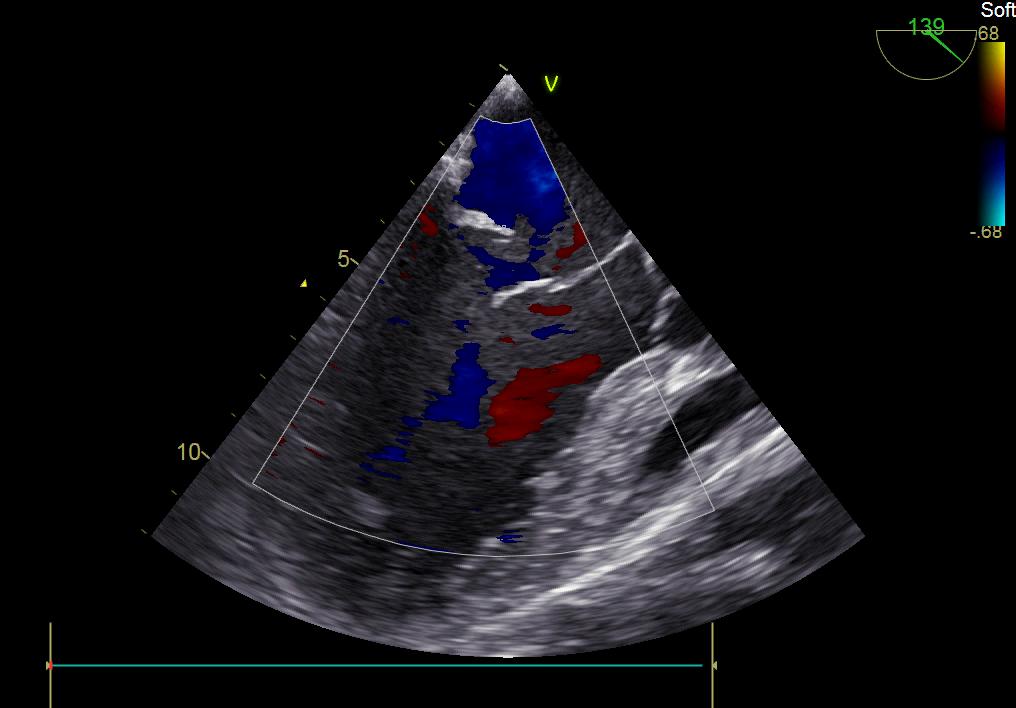

患者何某,42歲男性,因心功能不全入住我院心胸外科,心臟彩超提示二尖瓣后葉脫垂伴有重度返流及心臟擴(kuò)大,在迅速糾正心衰后,手術(shù)便提上日程,心胸外科廖金文主任多次組織全科及兄弟科室討論,在二尖瓣置換及成形術(shù)上,最終決定采取二尖瓣成形術(shù)。為保證手術(shù)安全,討論圍手術(shù)期各個細(xì)節(jié),所謂細(xì)節(jié)決定成敗,因?yàn)樾g(shù)前的細(xì)致全面,加上術(shù)中的一絲不茍及術(shù)后的精細(xì)化管理,患者術(shù)后恢復(fù)順利,健康出院,復(fù)查心臟彩超未見二尖瓣返流。

術(shù)前彩超